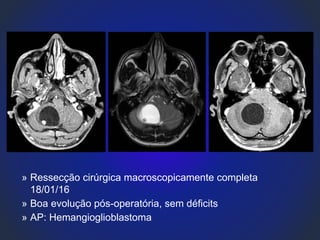

» Jan/16

» G.D.C., masculino, 23 anos, estudante.

» Cefaleia frontal em aperto associado a episódios de

vertigem

» Ressecção cirúrgica macroscopicamente completa

18/01/16

» Boa evolução pós-operatória, sem déficits

» AP: Hemangioglioblastoma